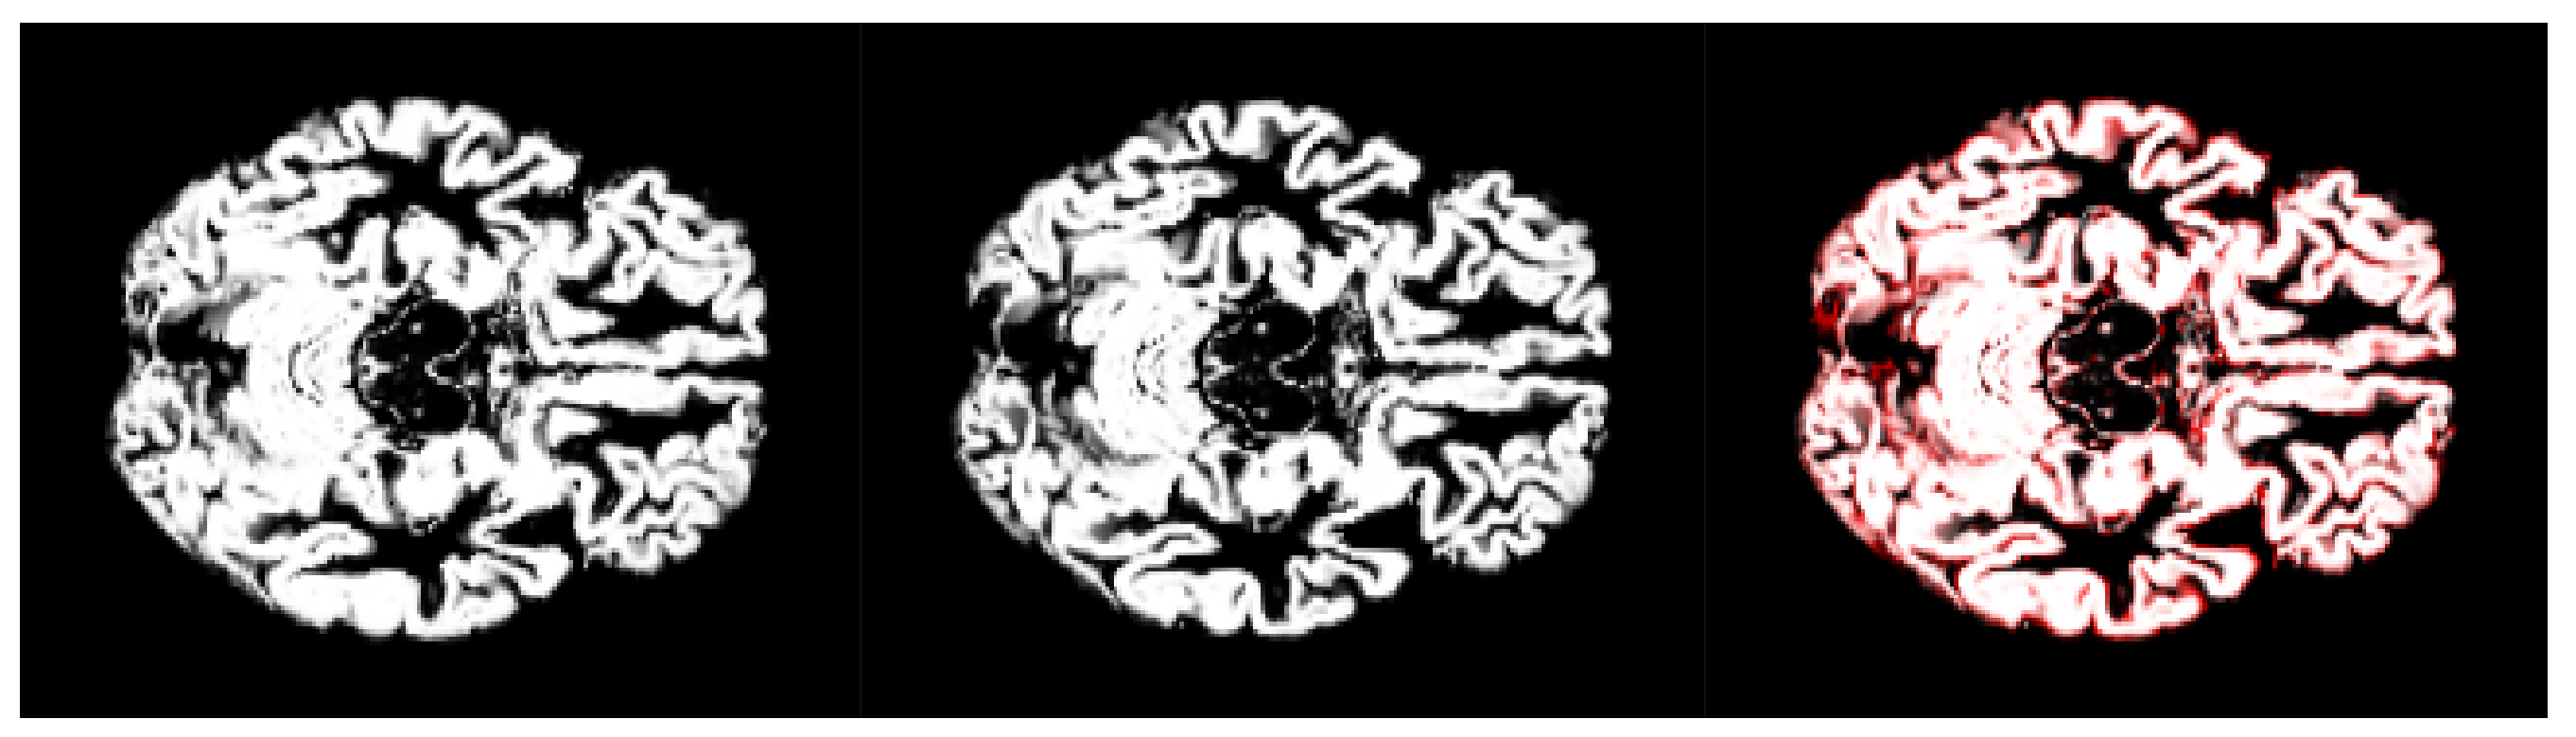

- We have introduced the notion of significant pixels, i.e., the pixels of the MRI images where the white (resp. gray) matter decays in the considered two-year time span, significantly differ between and subjects. The number of significant pixels, in the brain slices where the phenomenon mostly appeared, according to the different values obtained after performing a permutation test on all the pixels of the images, i.e., , , and , was about 4%, 2%, and 1.5% of the totality of the white matter and slightly more, i.e., 6%, 4%, and 2.5%, of the totality of the gray matter. Such a small number of significant pixels is sufficient to discriminate between and , as reported in Table 2 and Table 3, using the K-means clustering technique. Not surprisingly, when considering the white matter, all the and subjects were correctly clustered, i.e., the white matter decay of subjects significantly differed from that of ones. On the other hand, when considering gray matter, the subjects were correctly classified, while 6 of the 40 subjects were assigned to the class, with a percentage of error of 15%. This can be ascribed to the fact that Alzheimer’s disease strongly impacts on the white matter first, and later leads to the decay of the gray matter.We also underline that, according to the wide and consolidated literature, the most involved areas of the brain affected by Alzheimer’s decay are the medial portion of the temporal lobe, where the hippocampus, amygdala, entoryl cortex, and parahippocampal cortex reside. These areas are located inside the selected slice intervals where most of the significant pixels were detected. As an example, Figure 7 shows the significant pixels of slice 58, where a peak in the white and gray matter occurred, with the involved brain areas highlighted.

- Moving to the -to- predictive capability of the K-means model restricted to significant pixels, again we found different percentages according to the considered white or gray matter in the considered two-year time span. As expected, analyzing the white matter a high percentage of , namely, (Table 2), showed an pattern-like decay, similar to what was detected in [16,17,18] on the same dataset. So, our result, with a time span of two years, was slightly below the results presented in [20], where after one year only 8 of 37 patients with converted to (22%), verifying the reduction in the regional glucose metabolic rate, a truthful signal of early-onset .This high percentage of pattern in could be attributed to the similarly located decay of white matter in the two classes of subjects, as reported in [43]. This study involved 23 , 15 , and 15 subjects that underwent diffusion tensor magnetic resonance imaging (DTI), an advanced MRI technique extremely sensitive to white matter alterations. The authors found that patients with had an increase in mean diffusivity in the limbic, interhemispheric, cortico-cortical, and corticospinal tracts and, similarly, patients with showed an increase in axial diffusivity only in tracts projecting to the frontal cortex and splenium of the corpus callosum.On the other hand, time passing caused a milder effect on the gray matter of subjects, whose analysis revealed only 29% of -to- cases (see Table 3),, in accordance with the more optimistic studies in the work of [8], obtained through using machine learning techniques on fMRI images.Table 2 and Table 3 report the obtained statistics on the classification performance of subjects, together with the related indexes. In Figure 6, the distributions of subjects’ distances within the clusters show smaller distances between the subjects and the related centroids when white matter is considered with respect to gray matter. This implies that the classification using white matter produces tighter clusters and, consequently, a stronger accuracy than gray matter. All the clusters show some borderline subjects that produce small local maxima while moving away from the centroids. However, the computation of the Dunn indexes showed the high reliability of the obtained clustering. Again, we underline that the small diameter of the cluster may also be due to the smaller variability in the age range of the subjects. However, this does not constitute an issue in the final results of the research.